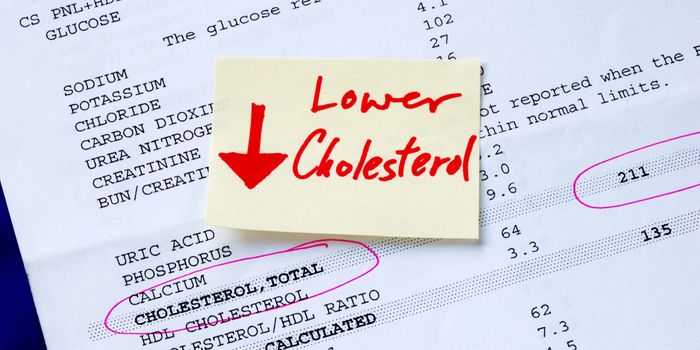

APR 20, 2016Health & MedicineFor atherosclerosis patients who experience a wide range of side effects to cholesterol-lowering drugs, an alternate opt ...